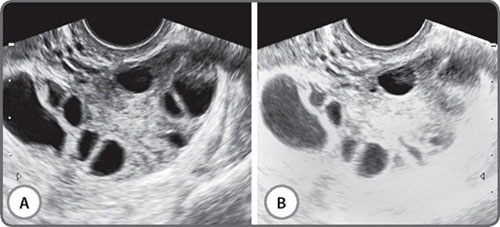

The vast majority of scans in fertility patients are transvaginal scans. Since the transducer is closer to the region of interest than with transabdominal scans, a higher transducer frequency can be used. This greatly enhances resolution. Currently available transducers employ frequencies of up to 12 MHz, and the difference in resolution is remarkable (Figs 1A and B). The trade-off with higher frequencies is of course, depth penetration of the beam, and these higher frequency transducers have a limited resolution beyond a certain distance from the transducer. This limitation can be overcome by using a multifrequency transducer. Console keys permit a choice of low, middle and high frequencies with the same transducer, enabling a great combination of resolution and depth. Transabdominal transducers have an advantage of a more panoramic field of view and a greater depth of penetration. These are therefore useful for identifying extraovarian adnexal structures and ovaries located at the pelvic brim. They are also indispensable for the assessment of associated abdominal lymph node disease, the suprarenal glands, kidneys, liver, abdominal peritoneal disease and the pleura.

Figs 1A and B: Images from the same patient using a (A) 5 Mhz and a (B) 12 Mhz transducer frequency. The inhomogeneous endometrium translates into an echogenic polyp. The indistinct posterior uterine wall on a higher frequency reveals an intramural fibroid. Thick-walled fluid loculi are evident posterior to the uterus on a high frequency study